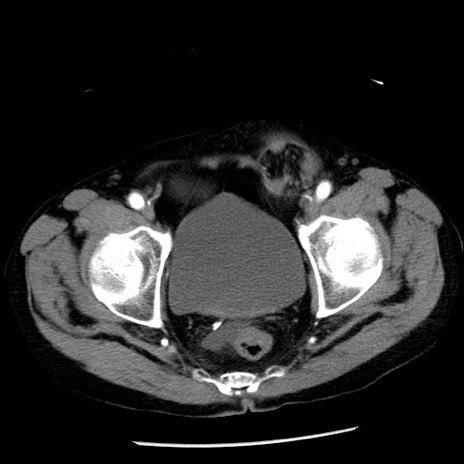

症例26(横断像)

【症例】80歳代男性

【主訴】嘔吐

【現病歴】昨晩2回嘔吐あり、今朝になっても嘔吐あり。来院。

【既往歴】胃潰瘍

【身体所見】意識清明、BT 37.6℃、BP 166/95mmHg、HR 100bpm、SpO2 97%、腹部:平坦・軟、腸蠕動音聴取良好、圧痛なし。

【データ】WBC 21900、CRP 1.46